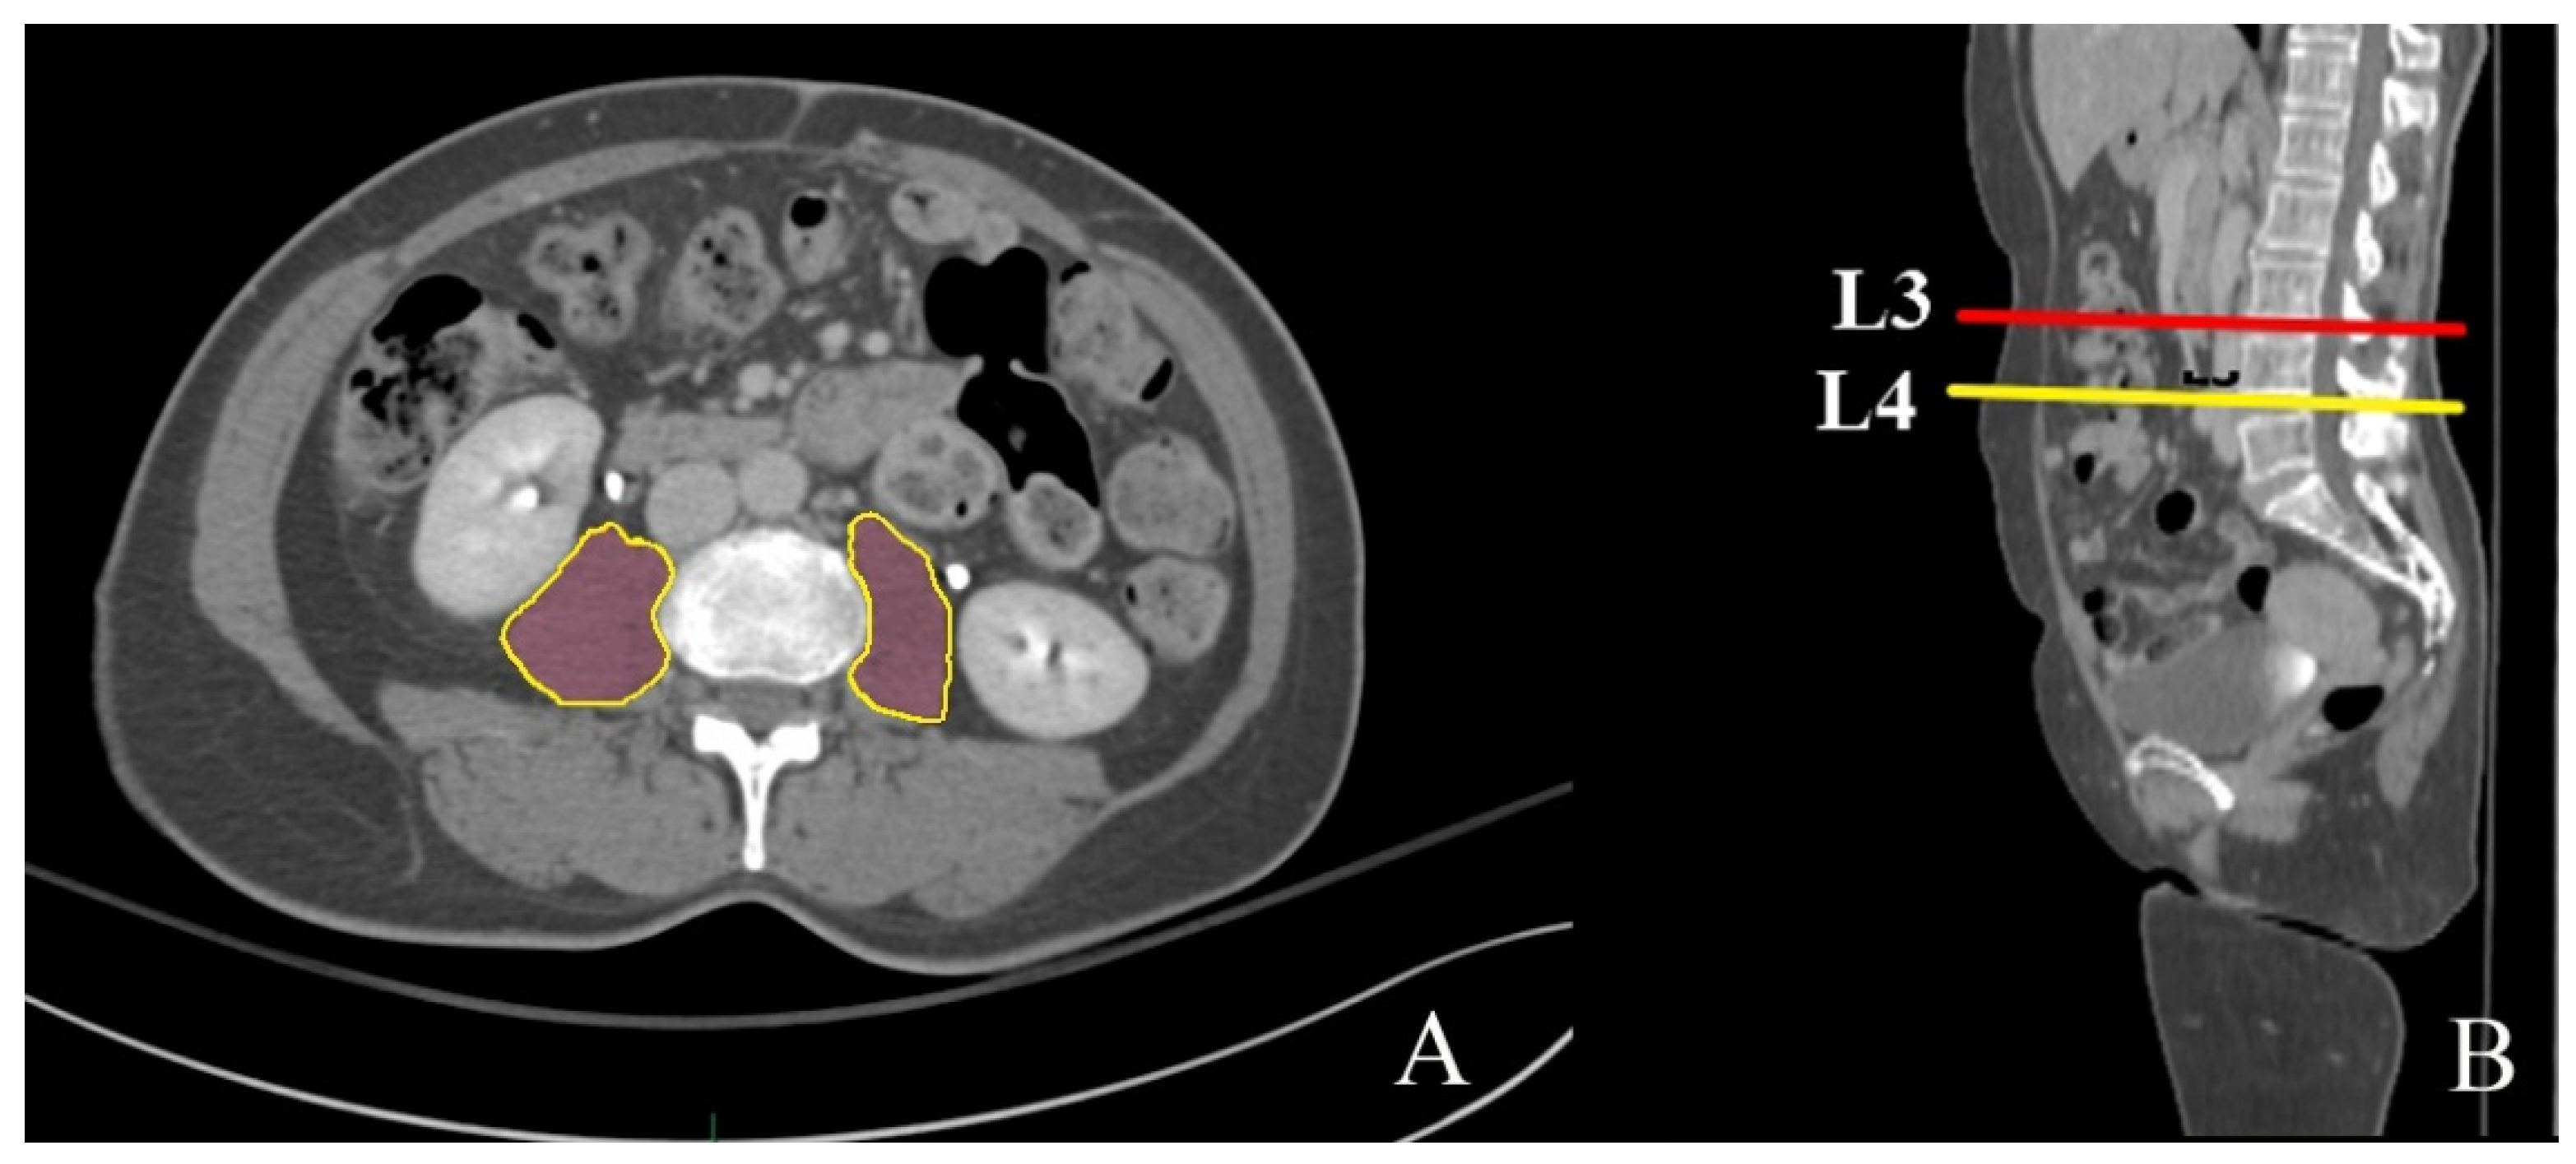

2.2.1. Psoas Muscle Segmentation and Volume Measurement